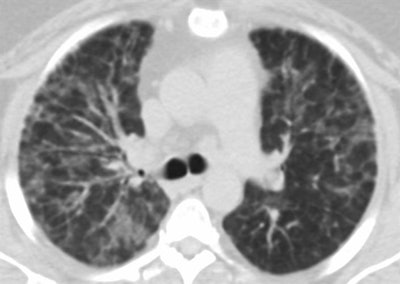

- Giant cell interstitial pneumonia: Hard metal contamination of vaping aerosols is well documented, the authors noted. They encountered one case of this rare pneumonia, which was due to trace amounts of cobalt in the patient's vape mechanism.

Giant cell interstitial pneumonia attributed to vaping in a 49-year-old woman who presented with one to two years of worsening dyspnea. Axial CT images show relatively symmetric ground-glass opacity and perilobular opacities involving all lobes. Subsequent surgical lung biopsy results were consistent with giant cell interstitial pneumonia. When asked about exposure, the patient said she had begun vaping a tetrahydrocannabinol (THC) mixture around the time her symptoms started. She had no other occupational exposures to heavy metals, and her vape pen was found to have traces of cobalt on subsequent analysis. Images courtesy of the American Roentgen Ray Society.Radiologists are an important part of the clinical team when it comes to patients presenting with lung injury, the researchers concluded.